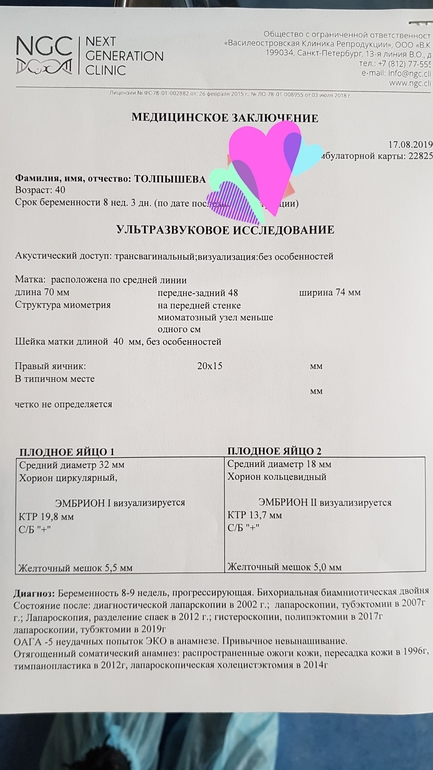

На втором фото, судя по методу Рамзи, мальчик. А на первом, кмк, девочка))) голосую за королевскую двойню! 💕

И мне кажется что королевская двойня ) Но главное чтоб были здоровы, и родились в срок , на пол согласна любой .

Зашла и я почитать что за метод Рамзи ?! Очень даже похоже на мальчика и девочку. Благодаря бб всё узнаешь ) Дай Бог чтоб всё было хорошо и родились в срок , это самое главное.